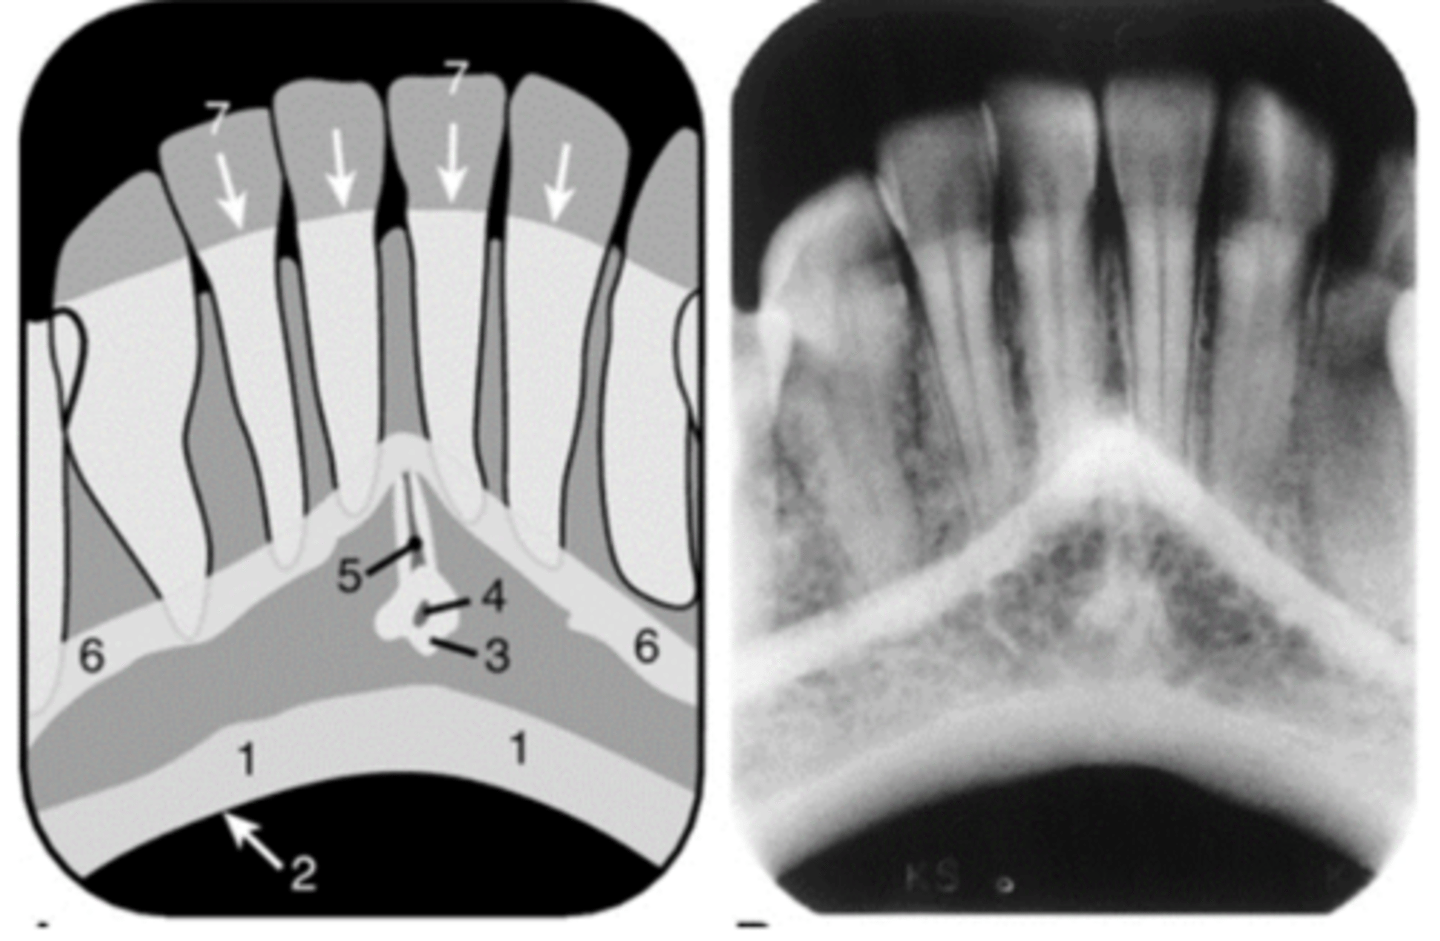

1

Intermaxillary suture (palatine suture)

2

Anterior nasal spine

3

Black arrow - Nasal septum

White arrow- nasal conchae

4

nasal aperture

5

Floor of nasal cavity

6

7

Incisive foramen

8

Nasopalatine canal

9

Superior foramina of the Nasopalatine canal

10

Lateral fossa

11

Nose (Soft tissue)